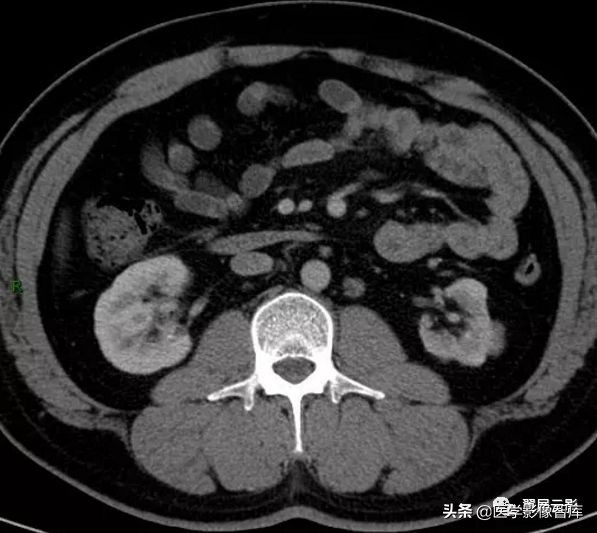

肾癌

肾癌最常见的肾恶性肿瘤,主要发生在中老年,男多于女,临床典型表现为无痛性血尿,肾癌可有假性包膜,血供丰富,大体病理切面为实性,常有坏死,出血和囊变,少数有钙化,晚期肾癌发生肾周脂肪囊和肾周各间隙的侵犯,淋巴结转移和肾静脉,下腔静脉瘤栓。

MRI表现:T1WI肾癌一般呈低信号,等信号时容易漏诊,此时仅见局部皮髓质交界的消失,冠状面对于肾脏轮廓的显示更清晰;T2WI肾癌一般为不均匀较高信号,但有时为等信号或较低信号,注意观察肾癌的假包膜,T1WI和T2WI均为低信号,增强扫描为必须检查项目,可有不同程度和形式的增强,对于肾盂肾盏受压和肾周肾窦脂肪受侵,淋巴结转移或肾静脉,下腔静脉瘤栓等情况也应观察描述,并进行肿瘤的分期。